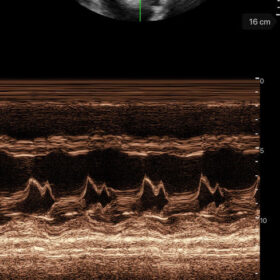

Mindray I3P WiFi Probe Image Gallery and Videos

Display mode: B, B/M, and Color, PW, PDI